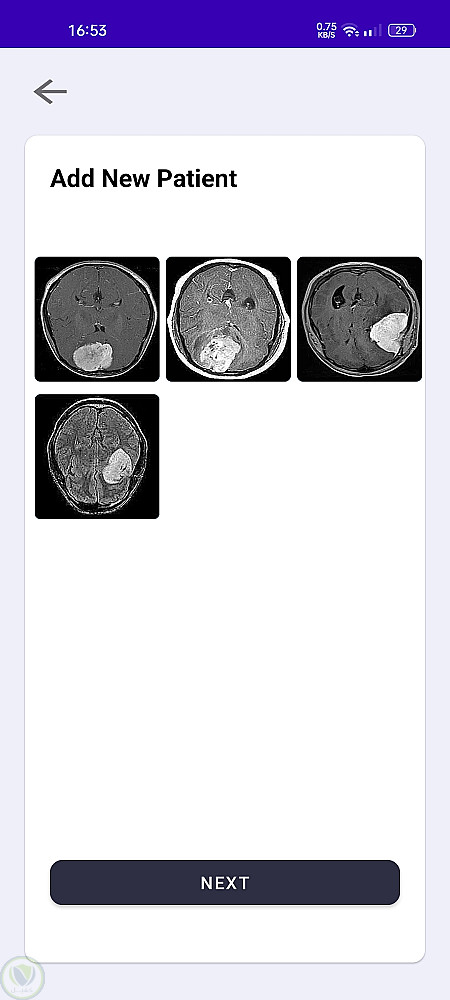

يتيح هذا التطبيق للمستخدمين رفع صور أشعة الرنين المغناطيسي للكشف عن أورام الدماغ باستخدام نماذج تعلم الآلة. يمكن للمستخدمين إدارة بيانات المرضى، والتواصل مع الأطباء عبر الدردشة، وحفظ التقارير للرجوع إليها لاحقًا